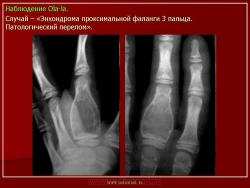

Энхондрома (син.: хондрома, центральная хондрома) — доброкачественная хрящевая опухоль, расположенная в костномозговом канале (интрамедуллярно). Встречается в 10 % случаев от общего числа доброкачественных опухолей костей. Считается, что она возникает из эктопически расположенных островков хряща, отщепившегося от пластинки роста на ранних этапах онтогенеза. В ряде случаев опухоль остается бессимптомной и обнаруживается случайно при рентгенологическом исследовании. В других случаях возникают боль и припухлость. Обычно болезненными становятся все энхондромы фаланг. Наиболее частая локализация: фаланги, главным образом, пальцев кистей, проксимальный конец плечевой кости, проксимальный или дистальный концы бедренной кости. При рентгенологическом исследовании в энхондроме определяются просветления с участками минерализации. Тень кости становится более широкой, кортикальный слой сохраняет целостность, но истончается. В редких случаях энхондрома имеет вид эксцентрически растущего экзофитного новообразования. Макроскопически опухоль представляет собой голубовато-белую полупрозрачную хрящевую ткань, в которую вкраплены желтоватые участки обызвествления. Опухоль состоит из отдельных хрящевых узелков, диаметр которых варьирует в пределах 1 см.

Энхондроматоз (син, болезнь Оллье) — редкая врожденная патология, не передающаяся по наследству, при которой у больных имеется множество доброкачественных хрящевых опухолей, главным образом на конечностях. Пораженная конечность укорачивается и деформируется. После завершения полового созревания заболевание не прогрессирует. Возможна малигнизация, которая отмечается в возрастном промежутке 13—69 лет. Локализация: энхондромы обнаруживаются в метафизах, диафизах, эпифизарных пластинках и суставных хрящах. Это интракортикальные и/или периостальные поражения в виде отдельных опухолей, не сливающихся друг с другом. Им присущ основной признак энхондроматоза — богатство клетками (гипериеллюлярность), причем встречается много двуядерных хондроцитов. И гиперцеллюлярность, и цитологическая атипия при энхондроматозе выражены значительнее, чем при солитарной энхондроме.